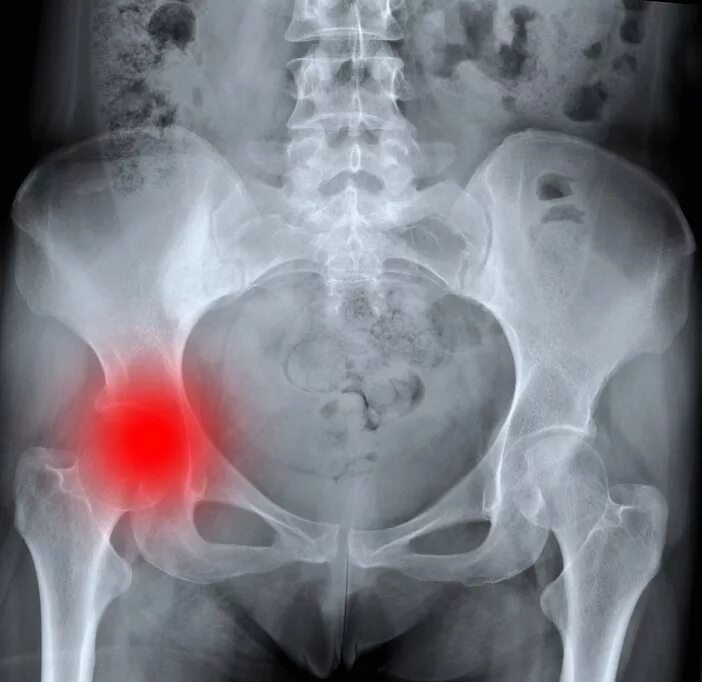

Метастазы в тазу